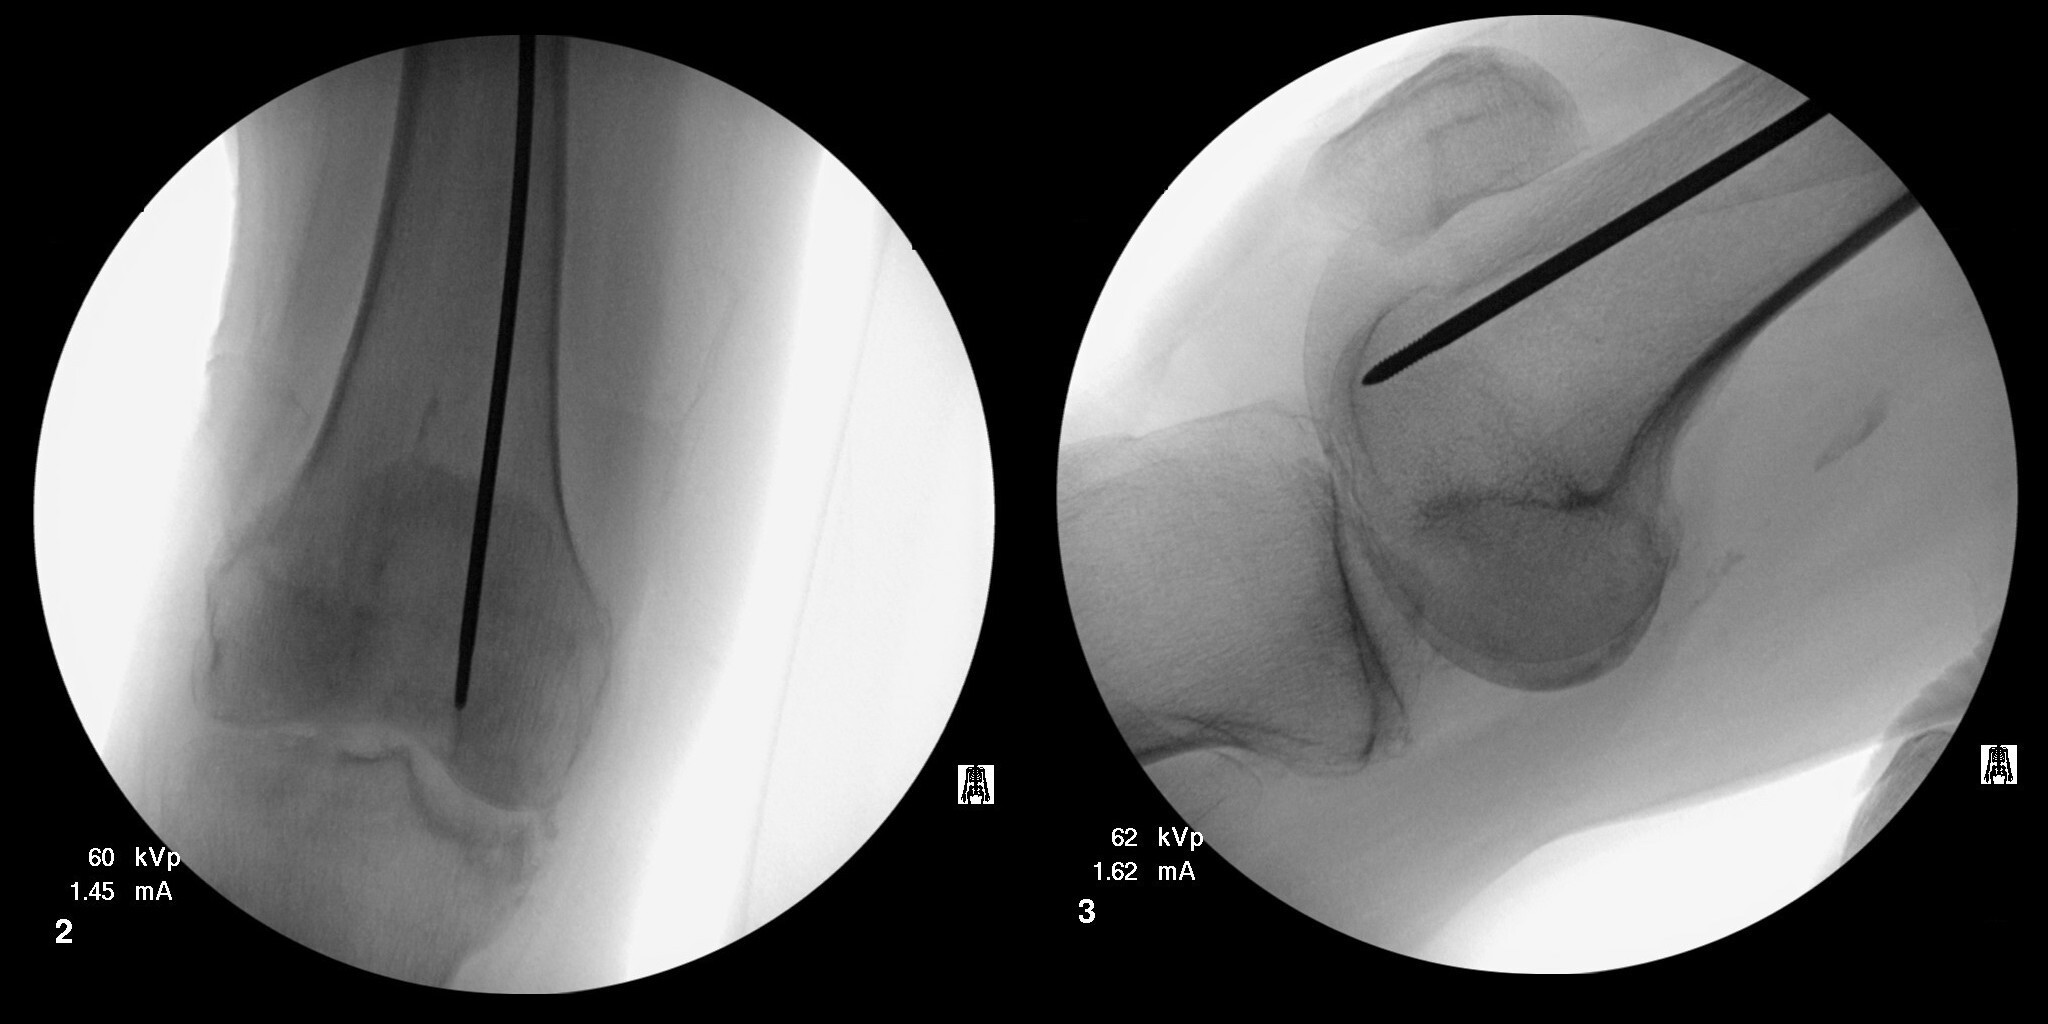

Multiple failed attempts were made to remove the guidewire using Kocher forceps, arthroscopic basket forceps, needle drivers, and Kerrison rongeurs (see Figure 1). Additional fluoroscopic images of the distal femur were subsequently obtained, revealing the guidewire to be inadvertently impacted into the subchondral bone of the distal femoral condyle (see Figure 2). Due to the inability to retrieve the guidewire using other extraction methods, a decision was made by the surgeons to remove the guidewire antegrade through the distal femoral condyle.

Traction on the operative leg was first released. The knee was then flexed to approximately 30° and held in the flexed position by a surgical assistant. A bone tamp was placed into the opening of the proximal femur and placed in direct contact with the guidewire (see Figure 3). A mallet was then used to gently tap the guidewire through the anterior aspect of the medial femoral condyle. The guidewire was advanced until tenting of the skin over the anterior knee was noted. A stab incision was made over the tip of the guidewire, and it was gently advanced further. Once enough guidewire was exposed, it was subsequently removed with a power drill.